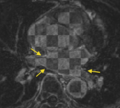

- Carma PV misreg.png 669 × 603; 268 KB